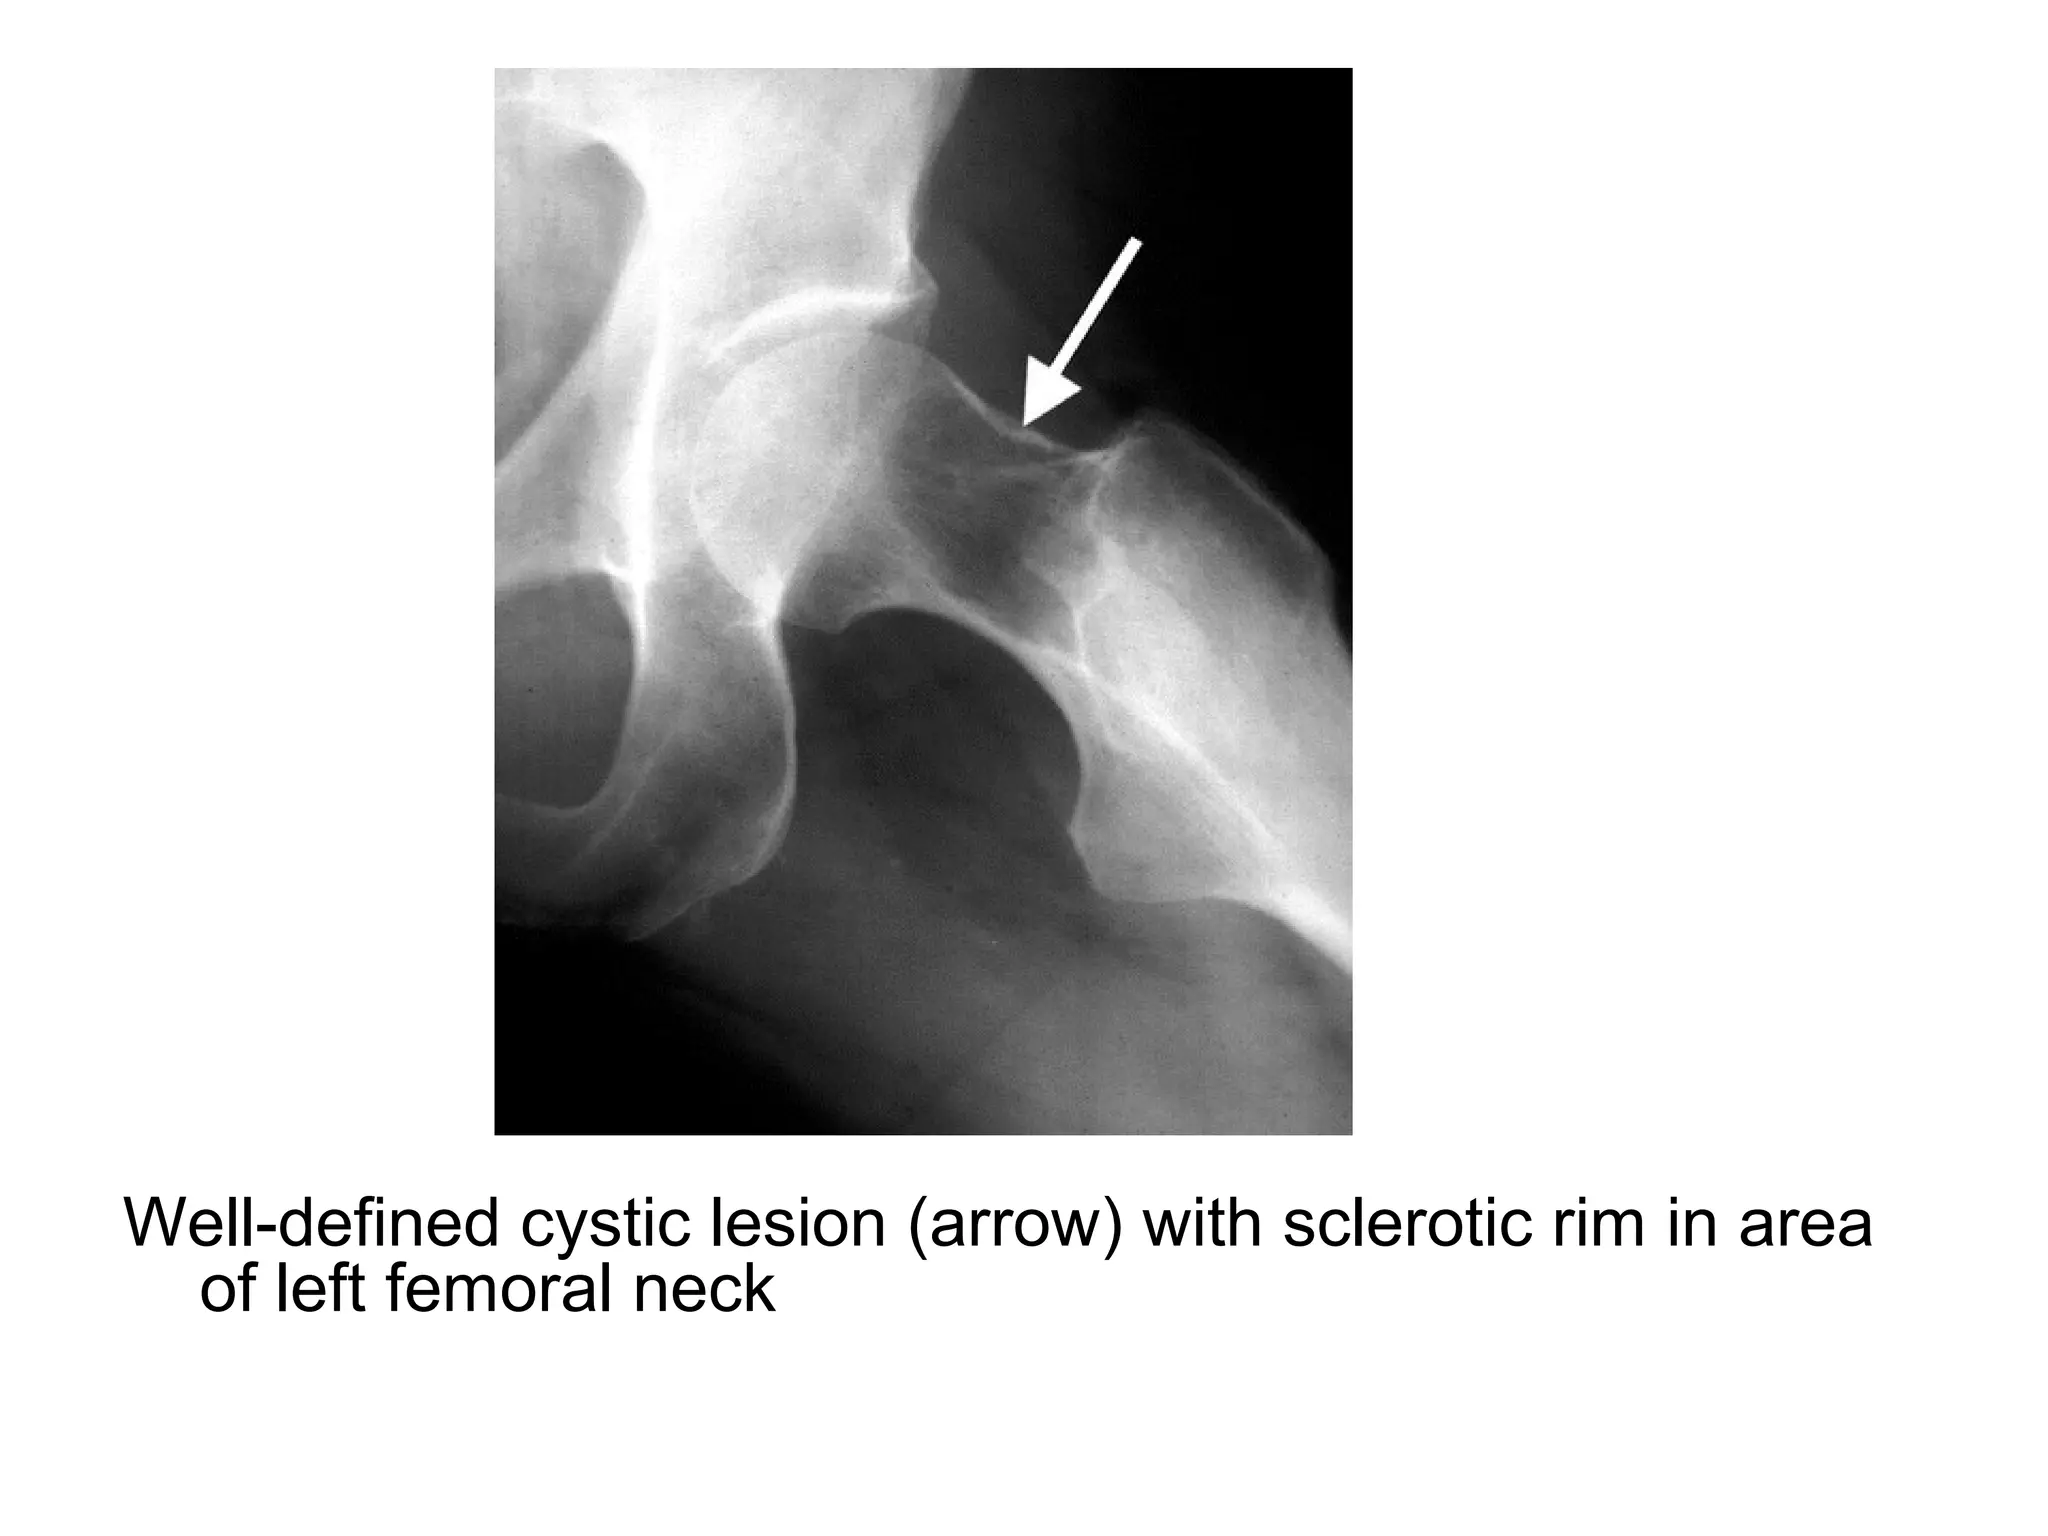

Well-defined cystic lesion (arrow) with sclerotic rim in area

of left femoral neck